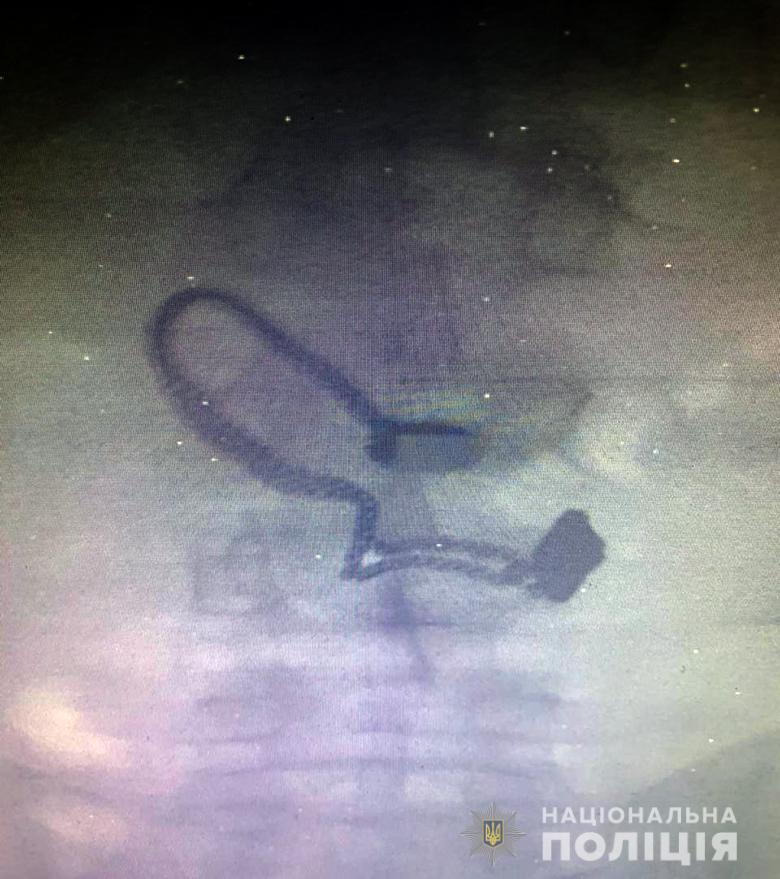

"Во время медосмотра на рентген-снимке задержанного врачи обнаружили украшение", - сообщают в полиции.